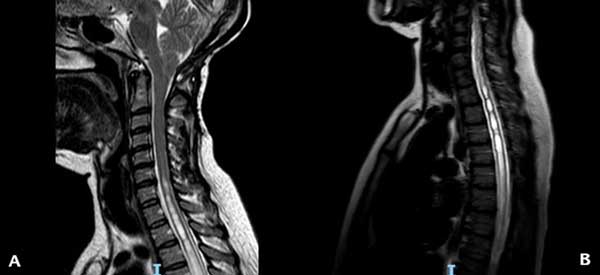

En el momento de la consulta, el examen físico presentó una leve paresia distal en ambos miembros superiores, hipoestesia termoalgésica en la mano y región subescapular izquierdas e hiperreflexia en ambos miembros inferiores. La resonancia magnética (RM) de encéfalo y columna cervical mostró un descenso marcado de las amígdalas cerebelosas con siringomielia cervicodorsal (Figura 1). Luego de la administración de contraste, se observó un refuerzo difuso de las meninges y senos venosos compatibles con hipotensión intracraneana (Figura 2). Ante la sospecha de una fístula espinal espontánea de LCR, se decidió realizar un estudio contrastado intratecal para determinar el sitio de la pérdida.

Figura 1. RM ponderada en T2 que muestra en (A) el descenso amigdalino y la siringomielia cervical y en (B) la extensión de la siringomielia a nivel torácico.